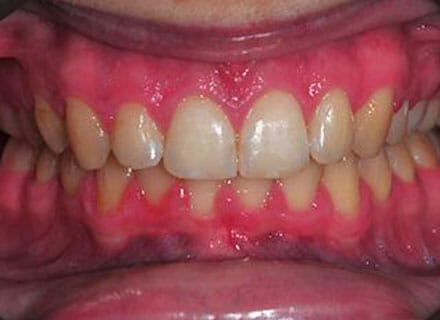

This lady came to us because she was unhappy with her crooked, uneven teeth.

The front ones were sticking out and she didn’t like her overbite. we were to move all the teeth sticking out back to where they should be, at the same time we made all the teeth nice and straight.

Treatment duration: about 12 months.

Brace Type: clear brackets